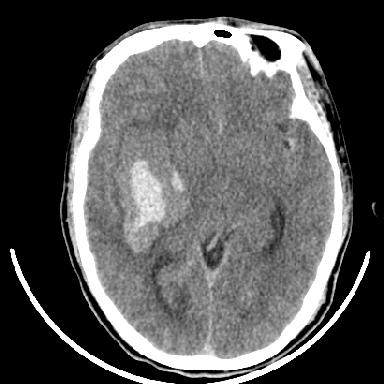

标题: CT6056:脑出血(血管畸形?) [打印本页]

标题: CT6056:脑出血(血管畸形?)

m 40突发头痛左侧偏瘫3小时

考虑高血压性脑出血,依据:

1是高血压性脑出血的好发部位,形态呈肾形,是高血压性脑出血的常见形状

2增强时占位效应加重了,考虑出血还没有停止

3病灶周围水肿不是太厉害,一般肿瘤出血水肿多非常明显

4病灶周围的‘软组织’影没有明显的强化

5至于脑血管畸形引起的出血,暂时没有看到明显的畸形血管影,也不太支持

支持右侧基底节脑出血

右侧基底节区脑出血.

支持右侧基底节区(主要为外囊区)原发性脑出血。

另附部分资料:“血液溢出血管外形成血肿,其内含有大量血红蛋白、血浆白蛋白,球蛋白,因这些蛋白对x线的吸收系数高于脑质,故ct呈现高密度阴影,ct值达40~90h,最初高密度灶呈非均匀一致性,中心密度更高,新鲜出血灶边缘不清。基底节区血肿多为“肾”型,内侧凹陷,外侧膨隆,因外侧裂阻力较小,故向外凸,其它部位血肿多呈尖圆形或不规则形”

术中抽出40ml陈旧血液,血肿底部似见一条索血管影